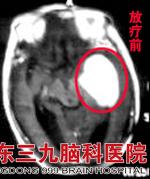

入院行头颅MR检查见:左侧颞部占位,大小约41cm×51mm,胸部X片示左侧肺门影增大增浓,胸部CT示考虑左肺下叶背段与后基底段多中心周围型肺癌伴左肺门多发淋巴结转移可能。行经皮肺穿刺,活检组织病理示中-低分化腺癌,脑脊液细胞学检查下发现肿瘤细胞,确诊为肺癌脑转移。www.999brain.com

考虑到陈婆婆为颅内单发病灶,且病灶较大,专家建议其先接受手术治疗,但陈婆婆的家人考虑到她年纪较大,遂拒绝手术治疗。为减轻陈婆婆的症状,肿瘤综合治疗中心蔡林波主任决定先为其行分次X刀治疗。因患者病理EGFR突变阳性,同步开始易瑞沙靶向治疗,X刀治疗后行全脑放射治疗。治疗后陈婆婆症状明显改善,头痛等不适消失。www.999brain.com